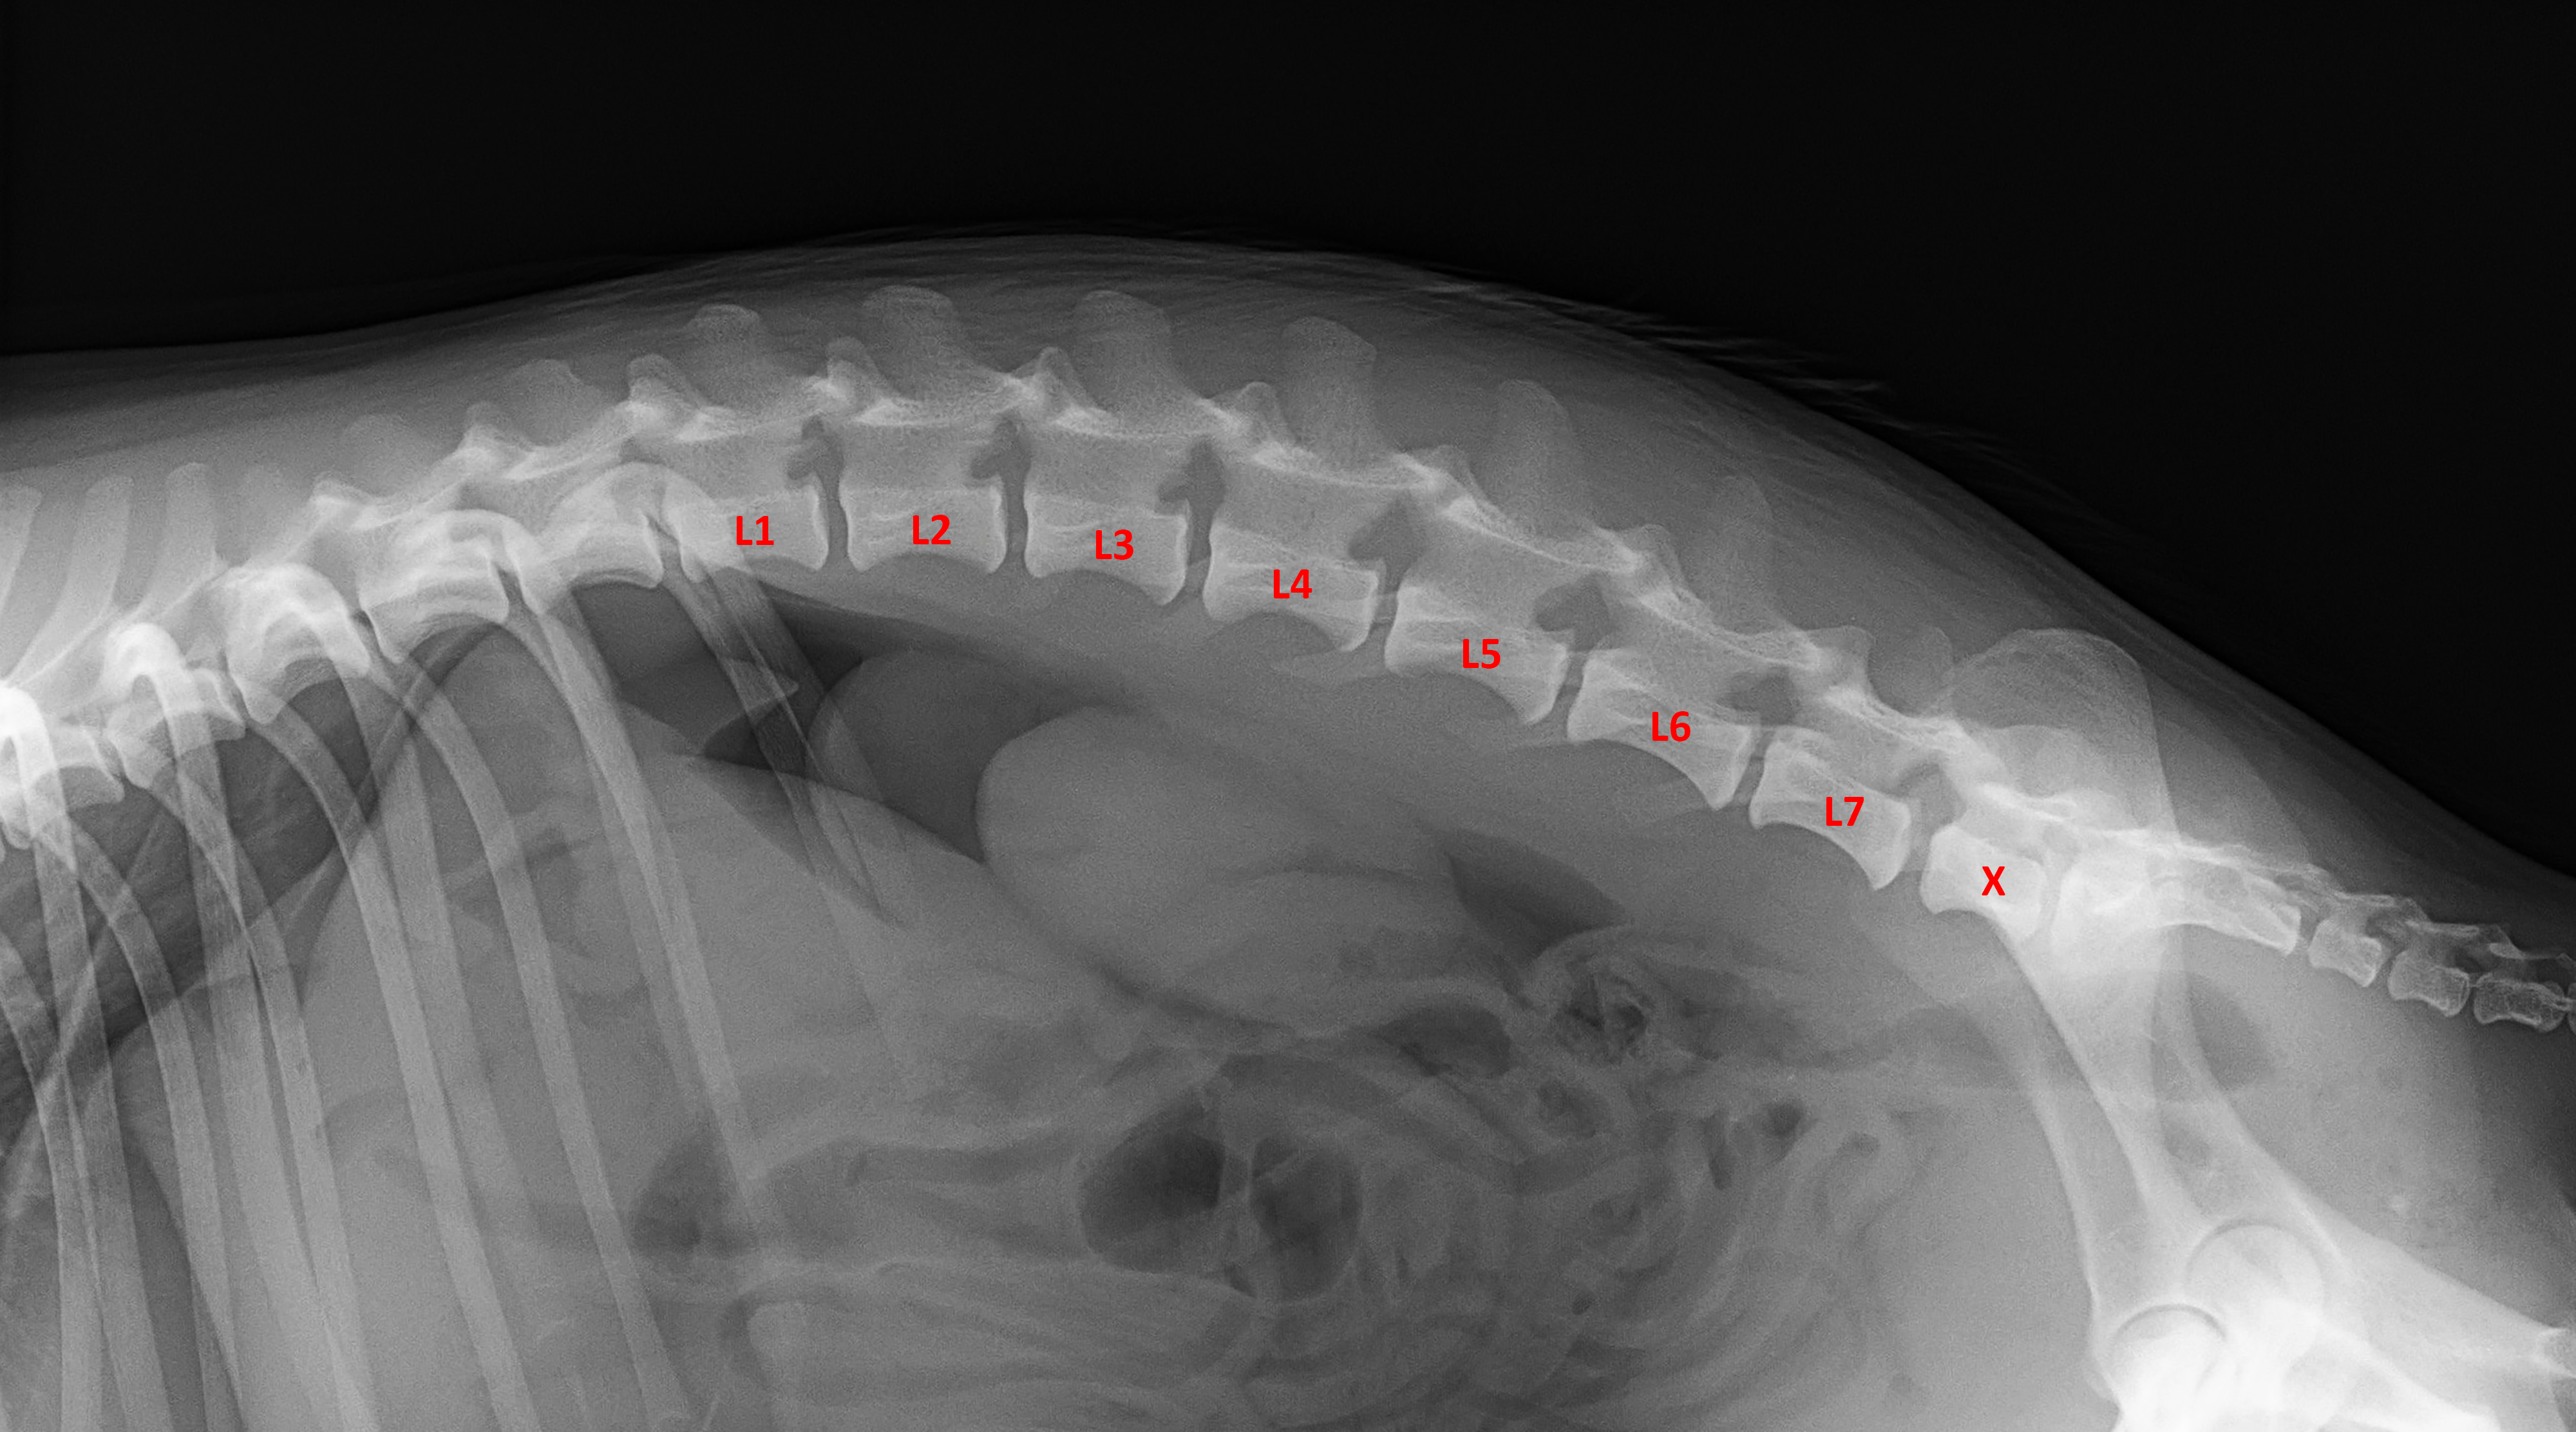

(2) 7 týdnů lat

(2) typ 3 I

(5) 7 měsíců lat

(5) typ 3 páteř VD

páteř LL

typ 3 u sedmiletého křížence